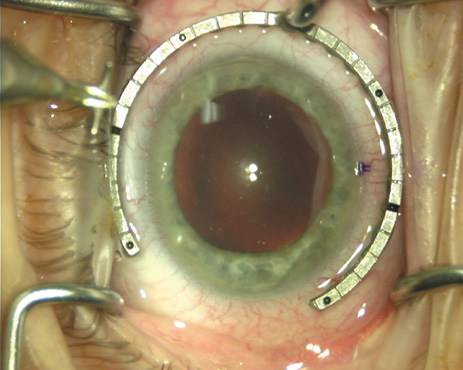

Case 1 is a 68-year-old male who presented for right cataract surgery. His refraction was −1.00 +2.25 × 80 and was recorded as reliable, consistent with his modest cataract density. Keratometry readings were 44.75 × 75 and 43.00 × 165. Corneal topography confirmed slightly more than 2.00 D of regular and slightly oblique cylinder. Consulting the nomogram, a plan was devised for a pair of LRIs to be centered over the 75-degree axis, with each incision delineating 45 degrees of arc. A single plane phaco incision was used and maintained at a size of less than 3.2 mm (Figs. 811).

Fig. 9. The broad hash marks of the fixation ring/gauge are centered over the 75-degree meridian, using the 6:00 limbal mark for orientation. Alternatively, a Mendez gauge may be used. (Reprinted from Hardten DR, Lindstrom RL, Davis EA. Phakic Intraocular Lenses: Principles and Practice. Thorofare, NJ: SLACK Incorporated, 2004, with permission.)

Fig. 10. The single footplate diamond blade is inserted perpendicular to the corneal surface and at the peripheral most extent of clear corneal tissue. In this case, the nomogram calls for arcuate incisions of 45 degrees. Therefore, the incision is begun approximately 22.5 degrees to one side of the broad hash mark. (Reprinted from Hardten DR, Lindstrom RL, Davis EA. Phakic Intraocular Lenses: Principles and Practice. Thorofare, NJ: SLACK Incorporated, 2004, with permission.)

Fig. 11. Opposite relaxing incision is completed. (Reprinted from Hardten DR, Lindstrom RL, Davis EA. Phakic Intraocular Lenses: Principles and Practice. Thorofare, NJ: SLACK Incorporated, 2004, with permission.)